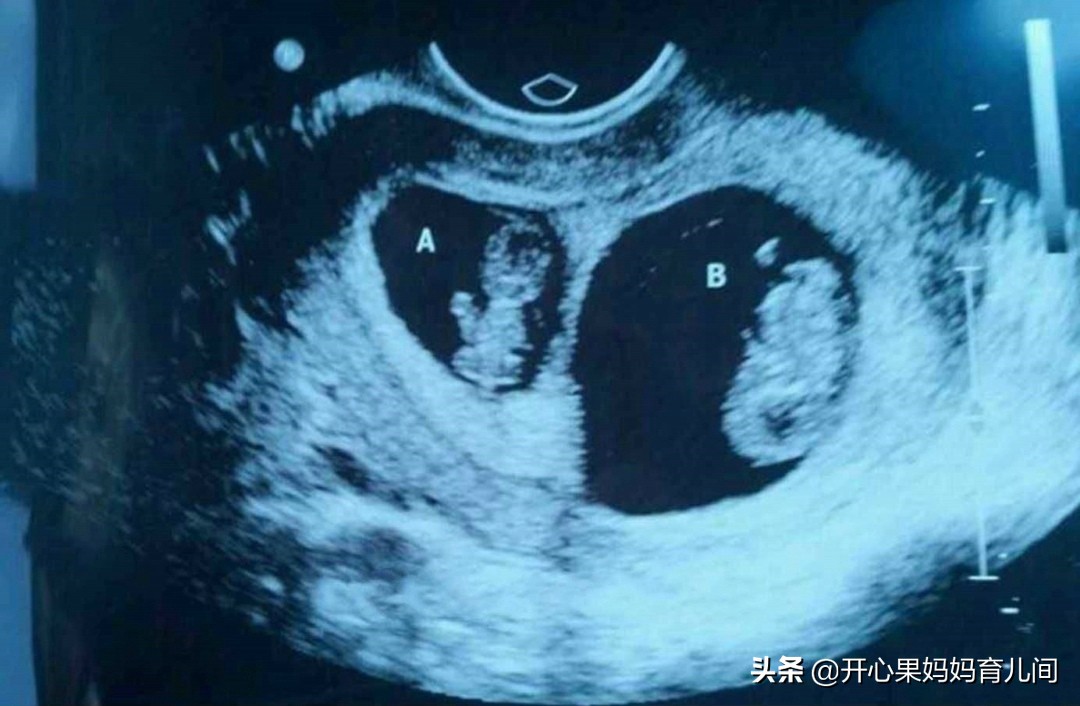

婚后一年,一直无法自然受孕,梅丽夫妻便去检查,梅丽和老公都有点问题。治疗了2年,依旧无法自然受孕,无奈之下,两人选择了试管婴儿。漫漫试管路,夫妻二人也实属不易,终于在第三次试管,也就是梅丽38岁时,怀上了双胞胎。

只是,夫妻俩没有欣喜太久,在孕6个月的时候进行四维检查,确诊双胞胎其中之一有心脏病,另一个手指脚趾有比较严重的残缺。这个消息击垮了夫妇二人,最终无奈,选择引产。